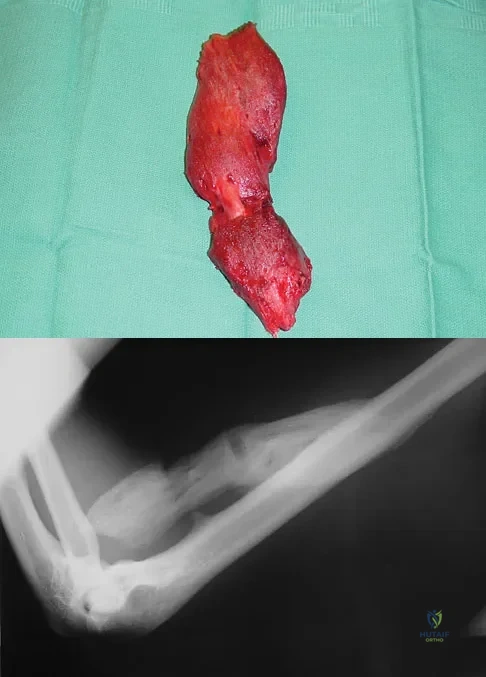

A 40-year-old man has a painful mass on his anterior ankle joint with limited range of motion. A radiograph, MRI scan, a gross specimen, and a hematoxylin/eosin biopsy specimen are shown in Figures 5a through 5d. What is the most likely diagnosis?

Explanation